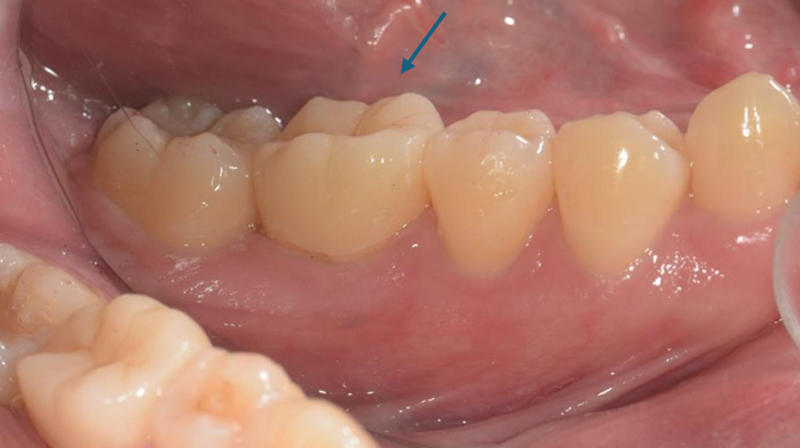

術前

術後完成假牙裝戴